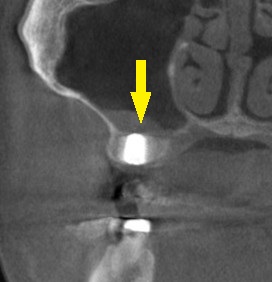

骨の状態を詳しく調べるために、CTを撮影してみると、骨の幅は十分ですが、高さが4~5mmと少なめでした(下の写真、2段目)。

下の写真、3段目が手術後のCTで、上方の上顎洞という空洞の粘膜を少し持ち上げるようにして、インプラントを埋入しました。